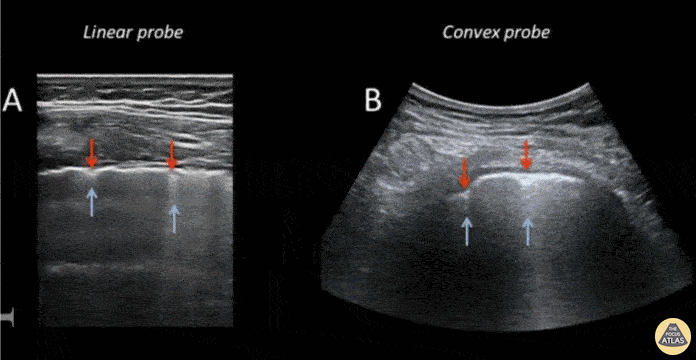

This still-shot image captures the differences in view as obtained using a linear vs curvilinear to assess a lung window. Submitted by Anibal Artero @ECOPULMONAR